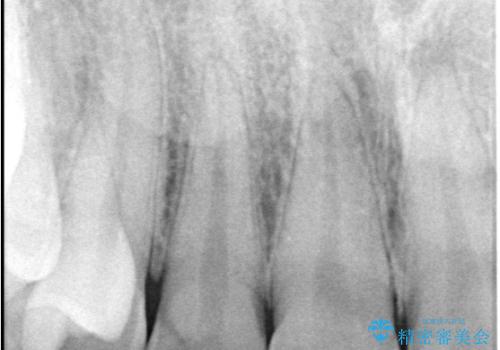

- 主訴:つい先日入れたセラミック(ジルコニア)ブリッジが奥歯部分で割れた。いつも同じ場所で壊れる。これで3度目。

セラミックに比べ、割れづらい金属(ゴールドでのブリッジのやり替えとなりました。

セラミックに比べ、破折リスクの少ない金属を使用したブリッジでのやり替えとなりました。

両支台歯が失活歯のため、どちらかもしくは両方の歯が破折した際、再度ブリッジを除去した治療が必要になるリスクとインプラント治療のご提案もさせていただきましたが、ブリッジでの治療を希望されました。

右下5番は支台歯CR築造を行っています。